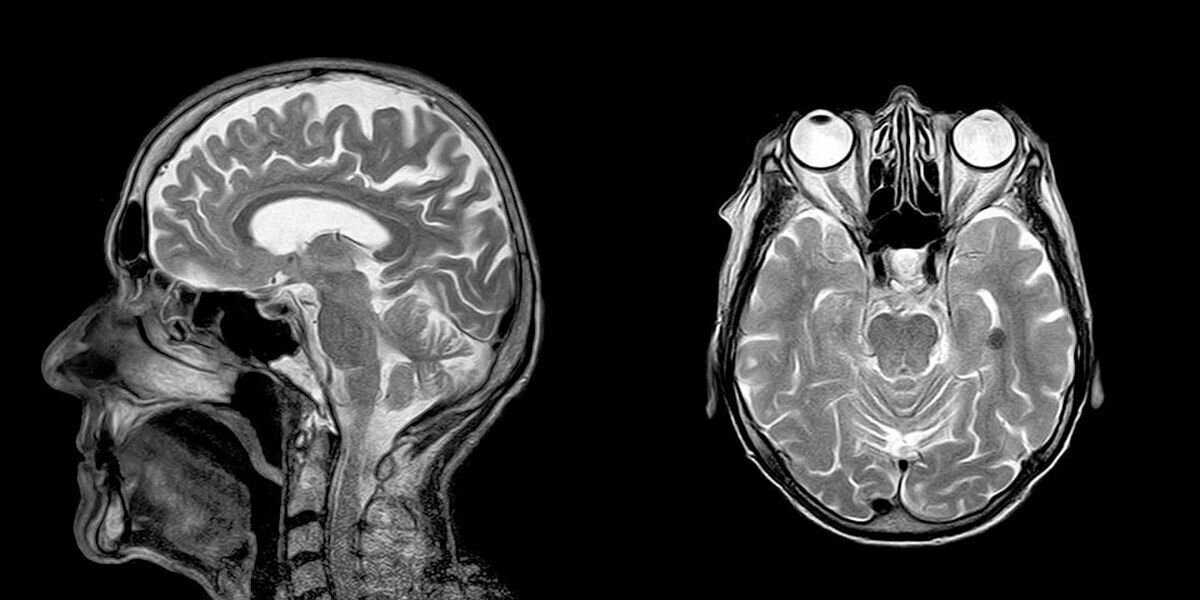

Шестилетний мальчик Ной, сын Шелли и Роба Уоллов из Великобритании, родился почти без мозга, однако выжил. История, в свое время удивившая даже специалистов, вновь привлекла внимание средств массовой информации.

Врачи выяснили, что черепная коробка зародыша была заполнена жидкостью, из-за которой мозг занимал лишь два процента,сообщает The Sun. Врачи сомневались в том, что ребенок, даже если он выживет, когда-нибудь сможет видеть, слышать, говорить и самостоятельно питаться. Тем не менее, родители приняли решение сохранить ребенка. Врачи провели операцию, в ходе которой откачали жидкость из черепа и спустя некоторое время мозг вырос примерно до 80 процентов от «обычного» размера, и все вышеперечисленное оказалось ему доступно. Отец ребенка признает, что отказаться от аборта родители решили, в том числе, из-за того, что на момент беременности они уже были не слишком молоды.

Сейчас Ною шесть лет. Самостоятельно ходить он пока не может, однако, как утверждают СМИ, он пытался заниматься серфингом и мечтает однажды покататься на лыжах. Внимание различных СМИ по всему миру он привлекает уже давно, и сами врачи характеризуют его историю как «выдающуюся».